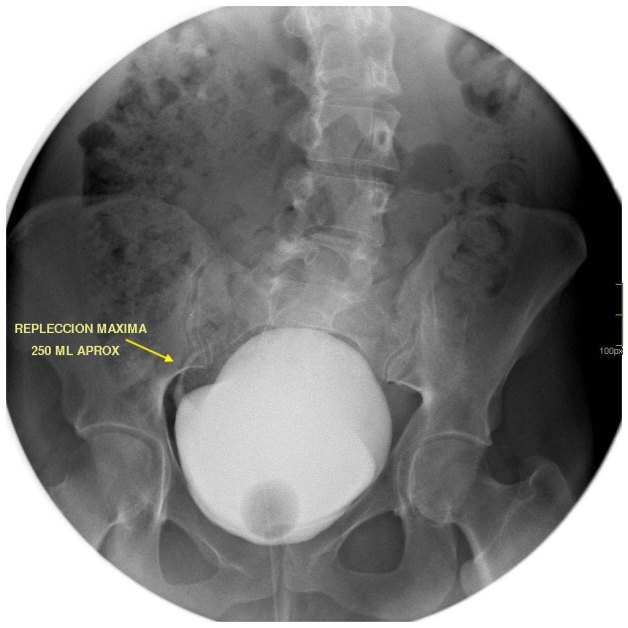

Cuando tu ves el estudio que te he enseñado, ¿Qué piensas?. Lo más normal es que pienses que el paciente, tiene una litiasis yuxtavesical izquierda, que observas en la placa simple de la imagen 2, corresponde con la imagen del TAC de Abdomen sin contraste, en la imagen 1. En el contexto de su patología, al paciente se le realiza una cistografía para valorar reflujo, que se demuestra en la imagen 3 y la imagen 4, donde puedes ver la existencia de reflujo en lado derecho, que tiñe el riñón derecho.

Finalmente, para hacerlo todo más verosímil, observas la ecografía donde ves cortes transversos y longitudinales donde ves una imagen hiperecogénica con una sombra posterior marcada, justo anclada la unión ureterovesical izquierda, al colocar el color en esa localización, podemos ver la típica imagen de artefacto de centelleo, que marca claramente la presencia de una litiasis en otros tanto estudios, imágenes 5 y 6.

Las flechas amarillas indican las regiones donde puedes encontrar la semiología que es la base del post de hoy.